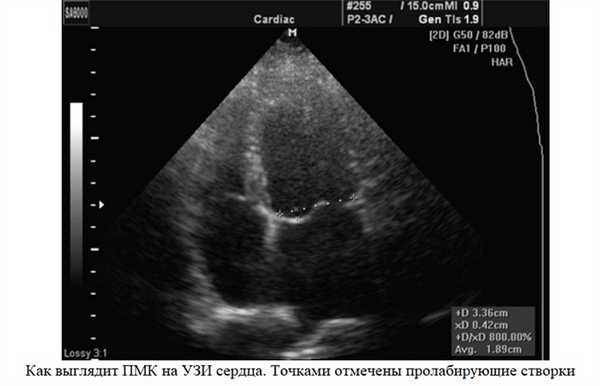

Эхокардиография (УЗИ сердца) – это главный метод исследования для диагностики ПМК. С его помощью оценивается тяжесть пролапса: степень пролабирования створок и регургитации. Под пролабированием подразумевается то, насколько створки клапана прогибаются в полость левого предсердия.

- смещение створок в момент систолы желудочков, пролабирование (прогибание) створок больше 3 мм.